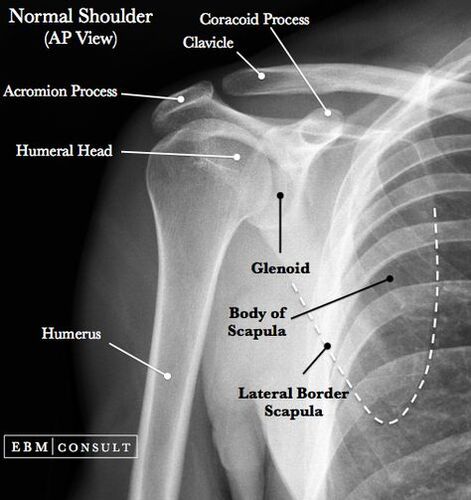

肩関節レントゲン写真のみかた,考え方

肩関節障害はアスリートや中高年に好発し、高齢者では転倒による上腕骨近位端骨折も頻度が高い疾患です。 この記事では肩関節のレントゲン写真の撮り方、見方について解説していきます。 今回の要約 外傷の際には正面像、スカプラY撮影が有用である。 オーバ…